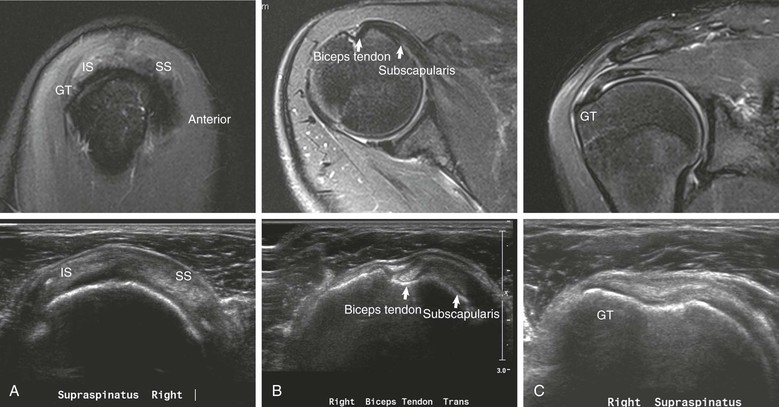

Sonography of the rotator cuff (Fig. 44-6) was first popularized in the 1980s as a simple and noninvasive method of evaluating the rotator cuff,26-30 and in recent years it has been repopularized as an accurate and cost-effective method for evaluation of the rotator cuff.31-35 Ultrasound examination of the shoulder requires a high-resolution transducer (7.5 to 10 MHz). Evaluation of the shoulder is performed with the patient in the sitting position. The examination begins with the arm in the neutral (thumb up) position. In this position, the bicipital tendon (see Fig. 44-6, A) is clearly visualized at the superolateral margin of the shoulder, and the presence or absence of fluid can be noted in the subacromial-subdeltoid bursa. Before evaluation of the rotator cuff, the shoulder is rotated internally, and the arm is placed behind the back. This maneuver results in retraction of the critical portion of the supraspinatus tendon from beneath the acromion, allowing maximal visualization of this portion of the rotator cuff.36 The rotator cuff should be evaluated in both the sagittal and coronal planes.

The normal rotator cuff (see Fig. 44-6) is sharply defined, uniform in thickness, and homogeneous in echo texture; it measures 4 to 6 mm in thickness anteriorly, and is normally somewhat thinner posteriorly.27 A thin echogenic band paralleling the upper surface of the cuff characterizes the subacromial-subdeltoid bursa.37 The overlying deltoid muscle is characterized by a speckled appearance that is distinct from the normal overlying cuff (Table 44-1).